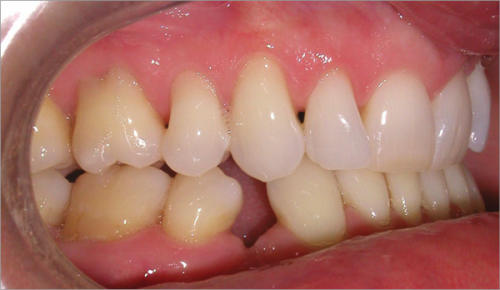

44 year old female:

Diagnosis:

- Upper and lower arch collapse due to missing teeth

- Retrusive angulation of upper & lower front teeth

- Severe collision and wear of front teeth